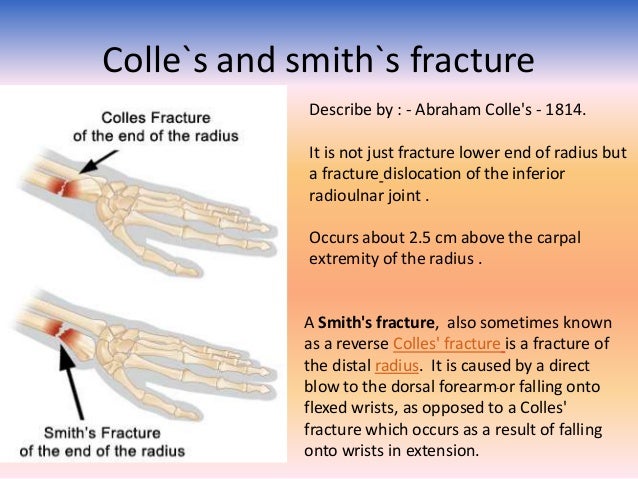

#Colles fracture smith fracture series

Ī wrist radiograph series is adequate for the characterization of a distal wrist fracture and can differentiate between a Colles and Smith fracture. Another cause of neurovascular compromise seen in Smith fractures and other distal radius fractures is acute compartment syndrome of the forearm. Less commonly, but still present neurological concerns include both radial and ulnar nerve compression. Up to 15% of these fractures may show symptoms of acute carpal tunnel syndrome (ACTS) from compression to the median nerve.

A compromise would necessitate immediate attempts at closed reduction. Įvaluation of the extremity's neurovascular status is imperative. There may also be an association of ulnar styloid base fractures. In addition to the volar displacement of the distal fragment, disruption of the distal radioulnar joint (DRUJ) and the triangular fibrocartilage complex (TFCC) often occurs. One of Smith’s first diagnostic criteria was a deformed wrist with swelling visible on the volar side and the prominence of the ulna along the dorsum of the wrist. Also, present on the exam are swelling, pain, and decreased ROM. The physical exam may reveal a deformity of the distal forearm, but the direction of angulation- dorsal (Colles) or volar (Smith) is difficult to discern on visualization. Data appears to support a direct correlation between low-energy trauma-induced distal radius fracture and decreased bone mineral density. Between the ages of 64 to 94, women are six times more likely than men to sustain this type of fracture. In the elderly population, distal radial fractures are the second most common fracture, second only to hip fractures. Almost all distal radius fractures arise in children sustaining high-energy falls and osteoporotic seniors who suffer low-energy falls. The highest incidence of Smith's fractures is in young males and elderly females. However, Smith fractures make up approximately 5% of all radial and ulnar fractures combined. Distal radial fractures are the second most common fracture in the elderly. With over 600000 cases annually in the United States alone, distal radial fractures account for more than 16% of all adult fractures and 75% of forearm fractures. The distal radius is the most common fracture site in the upper extremity.